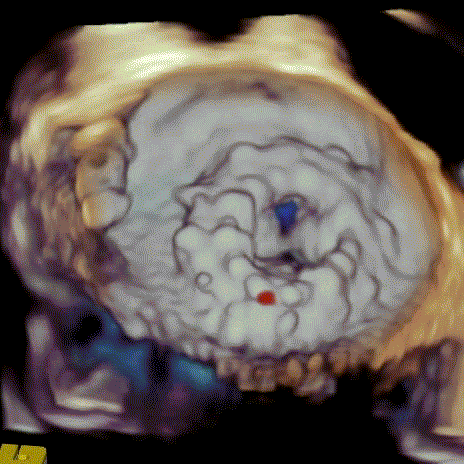

瓣中瓣植入前

二尖瓣重度反流